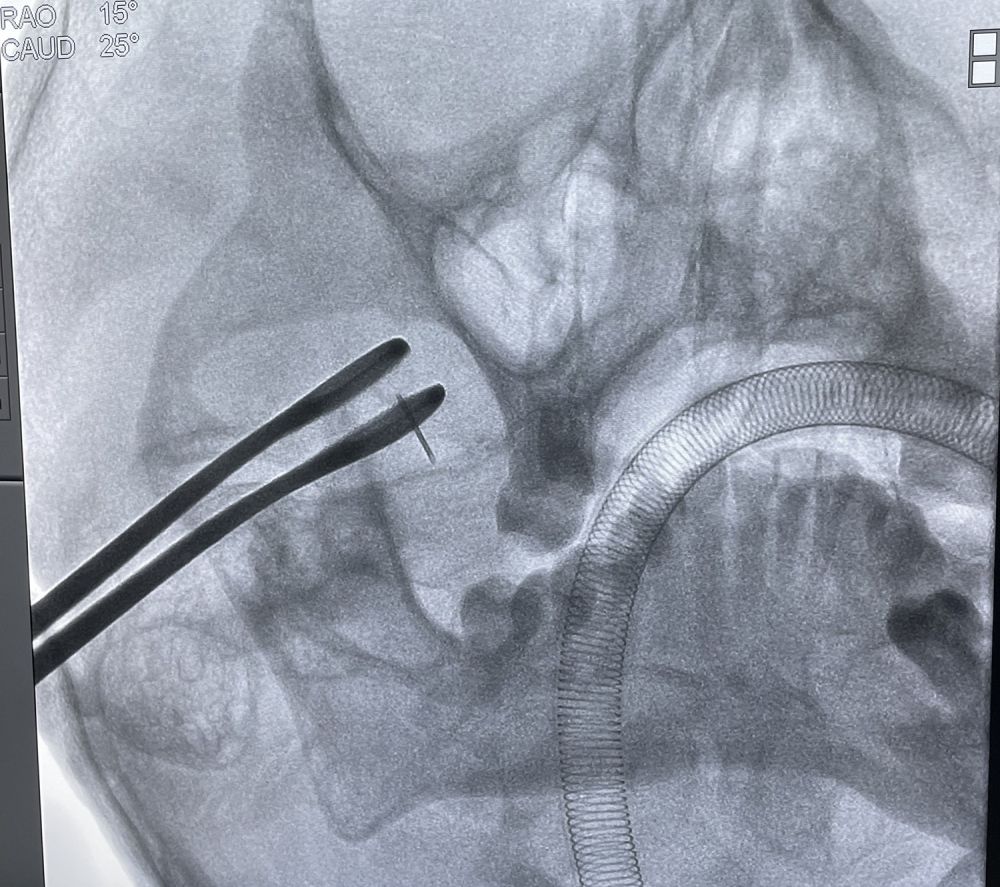

手术当天,神经外科医师团队在麻醉医师、手术护士的密切配合下,顺利行三叉神经半月节球囊压迫术。

文章插图

▲主治医生林育意正在术前准备